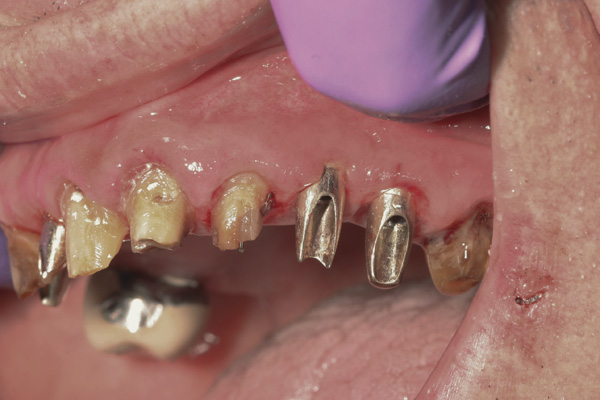

Case 3 – Remilling of Custom Abutments

Background: In this case, the patient had a failing mandibular and maxillary dentition due to caries secondary to radiation-induced xerostomia. The patient had had a radical neck dissection to remove a squamous cell carcinoma of the throat 9 years prior to his prosthodontic consultation with the authors. The patient reported a history of radiation therapy following surgery, but did not have a shielding stent. A staged approach was used so as to avoid removable prosthetics on his severely dry soft tissues. He chose to treat his mandibular issues first. Figure 9 shows healing abutments next to the temporarily retained natural teeth, and Figure 10 shows the first-stage custom abutments inserted with relatively good gingival contour and no recession. Recession was clearly seen around all first-stage abutments following adjacent extractions and second-stage implant placement (Figure 11).

Figure 11 Recession evident around first-stage abutments following adjacent extractions and second-stage implant placement.

Figure 11